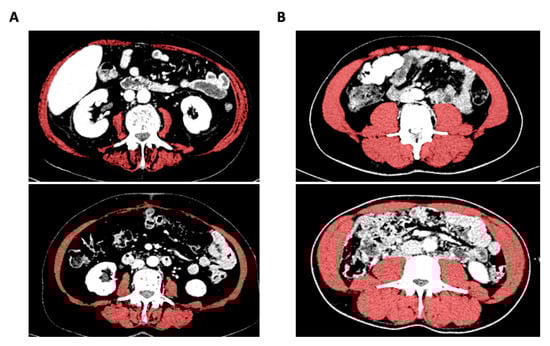

2.2. Analysis of Sarcopenia